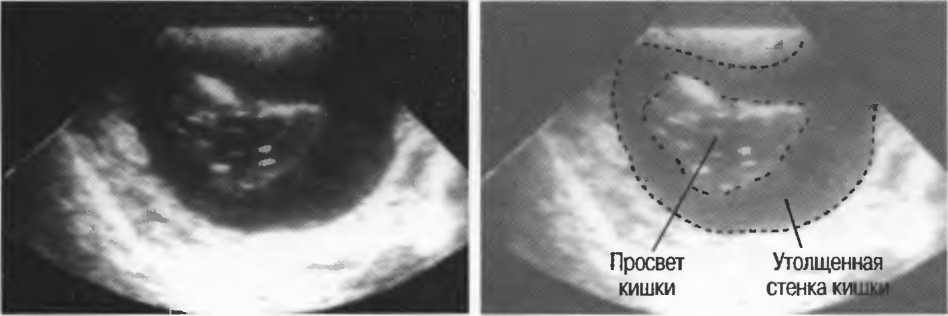

1. Подготовка

Пациент не должен пить и есть в течение 8 ч перед исследованием. Если жидкость необходима для предотвращения дегидратации, можно давать пациенту только воду. При острой симптоматике исследование можно проводить без подготовки. Детям, если позволяют клинические условия, пища и вода не даются в течение 3 ч до исследования.

При более углубленном исследовании, если нет клинических противопоказаний, может быть полезным дополнительный прием воды, особенно при исследовании поджелудочной железы, нижних отделов живота и таза.

2. Положение пациента. Пациент может лежать в удобной позе на спине. Под голову можно положить маленькую подушку, в случае выраженного напряжения передней брюшной стенки подушечку можно поместить также под колени пациента.

Намажьте живот гелем.

Пациенту разрешается дышать спокойно, однако при исследовании отдельных органов требуется задержка дыхания на вдохе.

3. Выбор датчика. Используйте датчик 3,5 МГц для взрослых и датчик 5 МГц для детей и худых взрослых. Предпочтительны конвексные или секторные датчики.

4. Установите правильный уровень общей чувствительности. Начинайте исследования, поместив датчик центрально в верхней части живота под мечевидным отростком и попросите пациента глубоко вдохнуть и задержать дыхание на вдохе.

Поверните датчик направо до того, как начнет визуализироваться печень. Отрегулируйте чувствительность, чтобы изображение имело нормальную однородную зхоструктуру. Должна быть хорошо различима высокоэхогенная линия диафрагмы сразу за задними отделами печени (рис. 27а).

Воротная и печеночные вены должны визуализироваться как трубчатые структуры с анзхогенным просветом. Стенки воротной вены высокозхогенны, но стенки печеночных вен практически не видны (рис. 276).

Рис.27а. Продольный срез. Неизмененная печень и диафрагма.